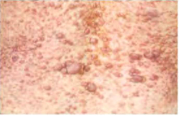

| 16:50, 11 באוגוסט 2014 | Melanoma-06.png (קובץ) |  |

119 קילו־בייטים | Motyk | 1 | |

| 10:07, 11 באוגוסט 2014 | Melanoma-05.png (קובץ) |  |

26 קילו־בייטים | Motyk | 1 | |

| 10:07, 11 באוגוסט 2014 | Melanoma-04.png (קובץ) |  |

23 קילו־בייטים | Motyk | 1 | |

| 10:07, 11 באוגוסט 2014 | Melanoma-03.png (קובץ) |  |

26 קילו־בייטים | Motyk | 1 | |

| 10:06, 11 באוגוסט 2014 | Melanoma-02.png (קובץ) |  |

24 קילו־בייטים | Motyk | 1 | |

| 10:06, 11 באוגוסט 2014 | Melanoma-01.png (קובץ) |  |

21 קילו־בייטים | Motyk | 1 | |